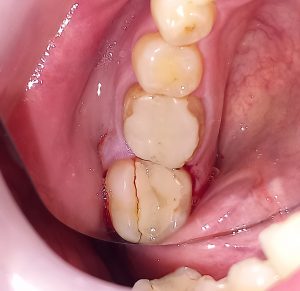

Τελική εικόνα μετά την ανασύσταση του δοντιού